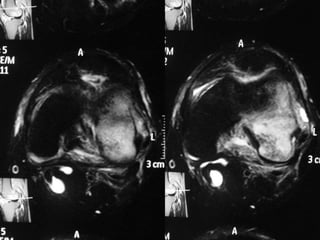

The document presents a detailed case study of a patient with transient osteoporosis of the hip (TOH) and spontaneous osteonecrosis of the knee (SONK) treated at Choithram Hospital & Research Centre in India. Over 20 years, the patient experienced multiple episodes of TOH and SONK with no history of trauma or co-morbidities, resulting in resolutions and recurrences of conditions. The information is intended for orthopedic surgery students and highlights personal experiences and case collections, with a disclaimer regarding content usage and potential controversies.